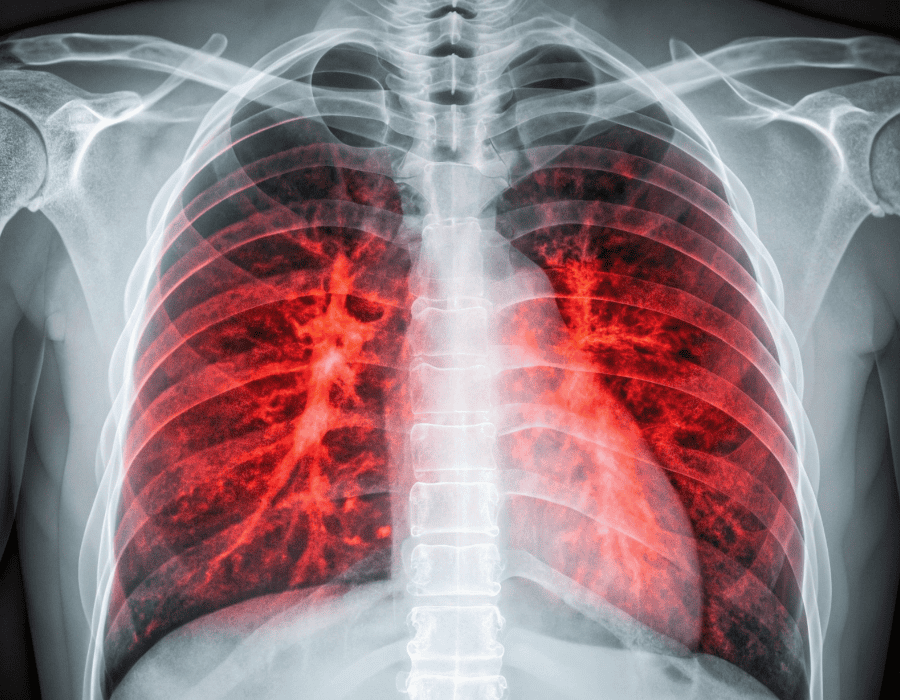

Chest congestion happens when mucus builds up in your lower airways or lungs, making it harder for air to move in and out freely. This can cause coughing, wheezing, tightness, or even a “crackling” sound when you breathe.

According to the Cleveland Clinic, congestion isn’t a condition itself — it’s a symptom of something else, like an infection or inflammation in your respiratory system. The body produces mucus to trap germs and irritants, but too much of it can clog your airways and make breathing uncomfortable.